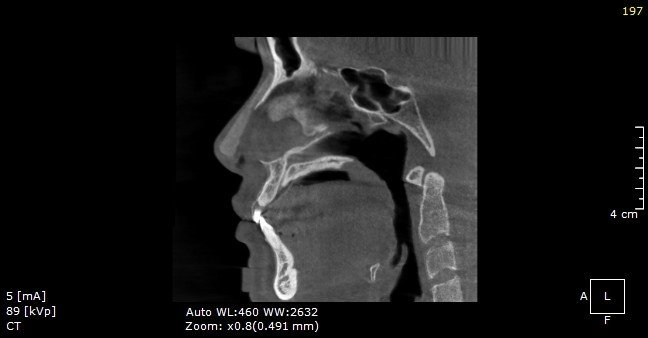

Vách ngăn lệch trái sâu của một khách hàng trên hình chụp CT 3D.

Điển hình, khi phân tích hình CT 3D của một khách hàng sửa mũi hỏng, BS.CKI Đinh Xuân Sơn Tùng cho biết: “Khách hàng này từng thực hiện phương pháp nâng mũi bọc sụn nhân tạo với vật liệu nâng là silicon. Da mũi bị mỏng ở phần giữa sống, phía trên bị vôi hóa và vách ngăn lệch trái, xiên phải. Bác sĩ sẽ tái tạo lại dáng mũi bằng phương pháp nâng mũi cấu trúc sụn tai, chỉnh vách ngăn, khắc phục tình trạng vôi hóa và bọc Megaderm để hạn chế mỏng da”.

Hình CT 3D của khách hàng có mũi bị hỏng phần giữa sống, phía trên bị vôi hóa và vách ngăn lệch trái, xiên phải.